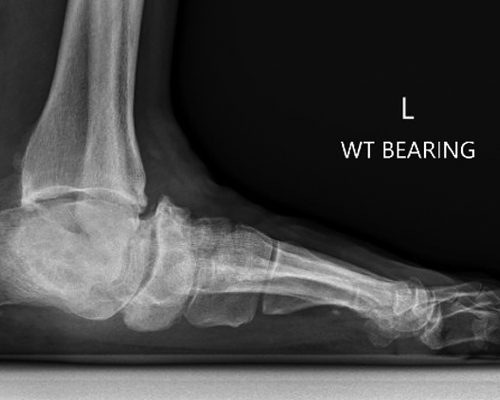

TOTAL ANKLE REPLACEMENT :: ORIF CALCANEUS :: ORIF ANKLE FRACTURE DISLOCATION :: COMPLEX BUNION AND LESSER TOE CORRECTION :: TALUS FRACTURE -1 :: TALUS FRACTURE -2 :: LISFRANC REPAIR :: COMPLEX TRIPLE ARTHRODESIS 1 :: COMPLEX TRIPLE ARTHRODESIS 2 :: MINIMALLY INVASIVE BUNION REPAIR 1 :: MINIMALLY INVASIVE BUNION REPAIR 2 :: ARTHROSCOPIC CARTILAGE REPAIR :: TENEX SPUR DEBRIDEMENT :: Haglunds Debridement and Achilles Repair